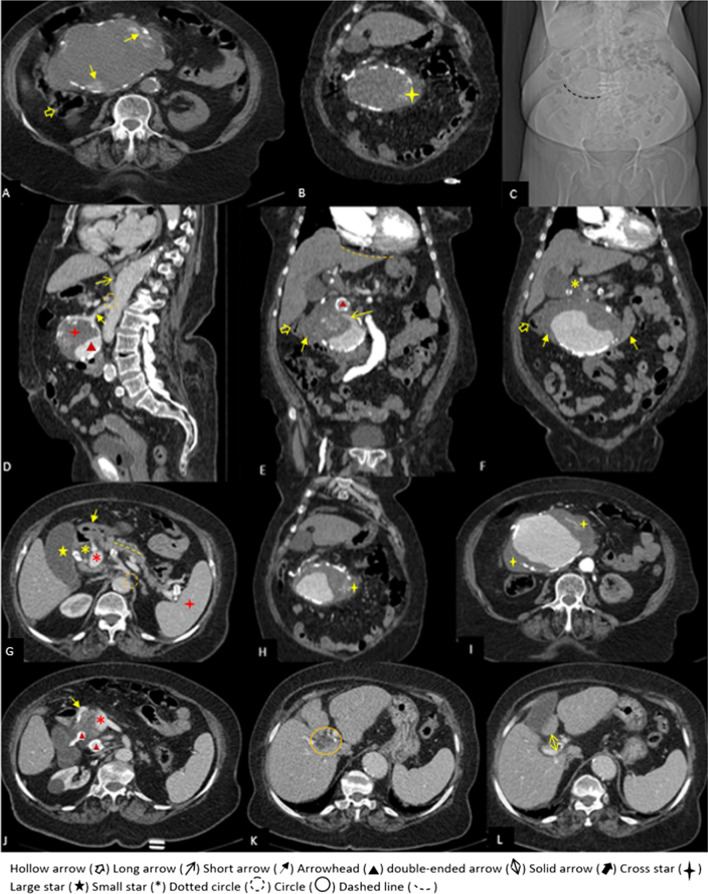

In the non-contrast CT that was done before the computed tomography angiography (CTA), there was a huge mass (14 × 10 × 9 cm) with peripheral discontinuous calcification near the head of the pancreas extending superiorly to the subhepatic region and inferiorly medial to the cecum and causing severe compression on D2 and D3 portion of the duodenum and the common bile duct (CBD). Moreover, marginal hyperdense crescent areas were present (Fig. 2A–C). After contrast injection in the arterial phase of CTA, the mass had a density like an aorta and originated superiorly from the posterior surface of the proximal portion of the SMA. The aneurysm was inferiorly connected to the tortuous atherosclerotic vessels around the head of the pancreas. These vessels superiorly originated from the gastroduodenal artery. All arterial branches supplying the bowel loops originated from own SMA, not from this aneurysm. These findings suggest that the huge aneurysm originated from the inferior pancreaticoduodenal artery, which was connected to SMA on one side and to anterior and posterior pancreaticoduodenal arteries on the other (Figs. 2D, 3A, C, D).

There was mural thrombosis in the aneurysm, which was accompanied by a linear extension of intraluminal contrast through the mural thrombosis, indicating a thrombosis fissuration sign (Fig. 2E). Discontinuous calcification of the aneurysm’s wall was present, and there were areas of focal bulging of the aneurysm’s lumen to the surrounding mesenteric fat, associated with mild stranding and minimal fluid in these areas. Two smaller aneurysms (2.5 × 2.5 cm and 1.5 × 1.2 cm) were also seen adjacent to the superomedial margin of the huge aneurysm, originating from the posterior branch of the gastroduodenal artery (superior posterior pancreaticoduodenal artery) (Figs. 2E, J, 3C, D). A significant narrowing at the origin of the celiac trunk was noted due to diaphragmatic crura compression, indicating median arcuate ligament syndrome (Figs. 1D, 2D, G, 3C).

Although there was no obvious evidence of the aneurysm’s rupture or extravasation of contrast but the presence of hyperdense crescent sign on non-contrast CT, thrombus fissuration sign on CTA, and areas of focal bulging of aneurysm’s lumen associated with adjacent fat stranding were impending rupture signs of aneurysm which all of them necessitates the early treatment.